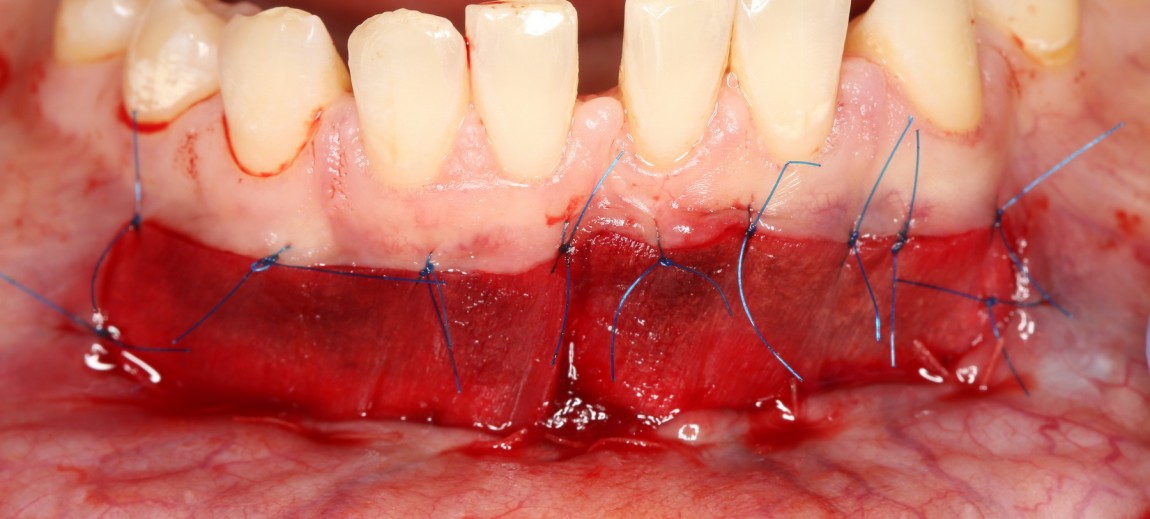

Тупым способом отслаиваются мягкие ткани до надкостницы. Ее очень легко определить — она, в отличие от других слоев, она неподвижно прикреплена к кости. Таким образом, создается ложе под матрицу Mucograft:

Следует учесть, что в процессе рубцевания рана немного стянется.

Поэтому, отслойка и сепарация тканей делается с небольшим запасом.

Теперь берем коллагеновую матрицу, примеряем ее:

Матрица Mucograft имеет два слоя: наружный плотный и внутренний более рыхлый. Так вот, материал фиксируется швами за наружный плотный слой. В данном случае, я использовал нерезорбируемый шовный материал Prolene 6-0 в верхнем участке раны и Vicrlyl 6-0 — в нижнем:

Вообще, лучше везде фиксировать нерезорбируемым шовным материалом. Просто снятие швов в области будущей переходной складки представляет известные сложности (врастают), и я решил облегчить жизнь пациентке и себе. Но делать так постоянно не рекомендую — использование резорбируемых плетеных шовных материалов, особенно в условиях некачественной гигиены, может привести к образованию лигатурных свищей.